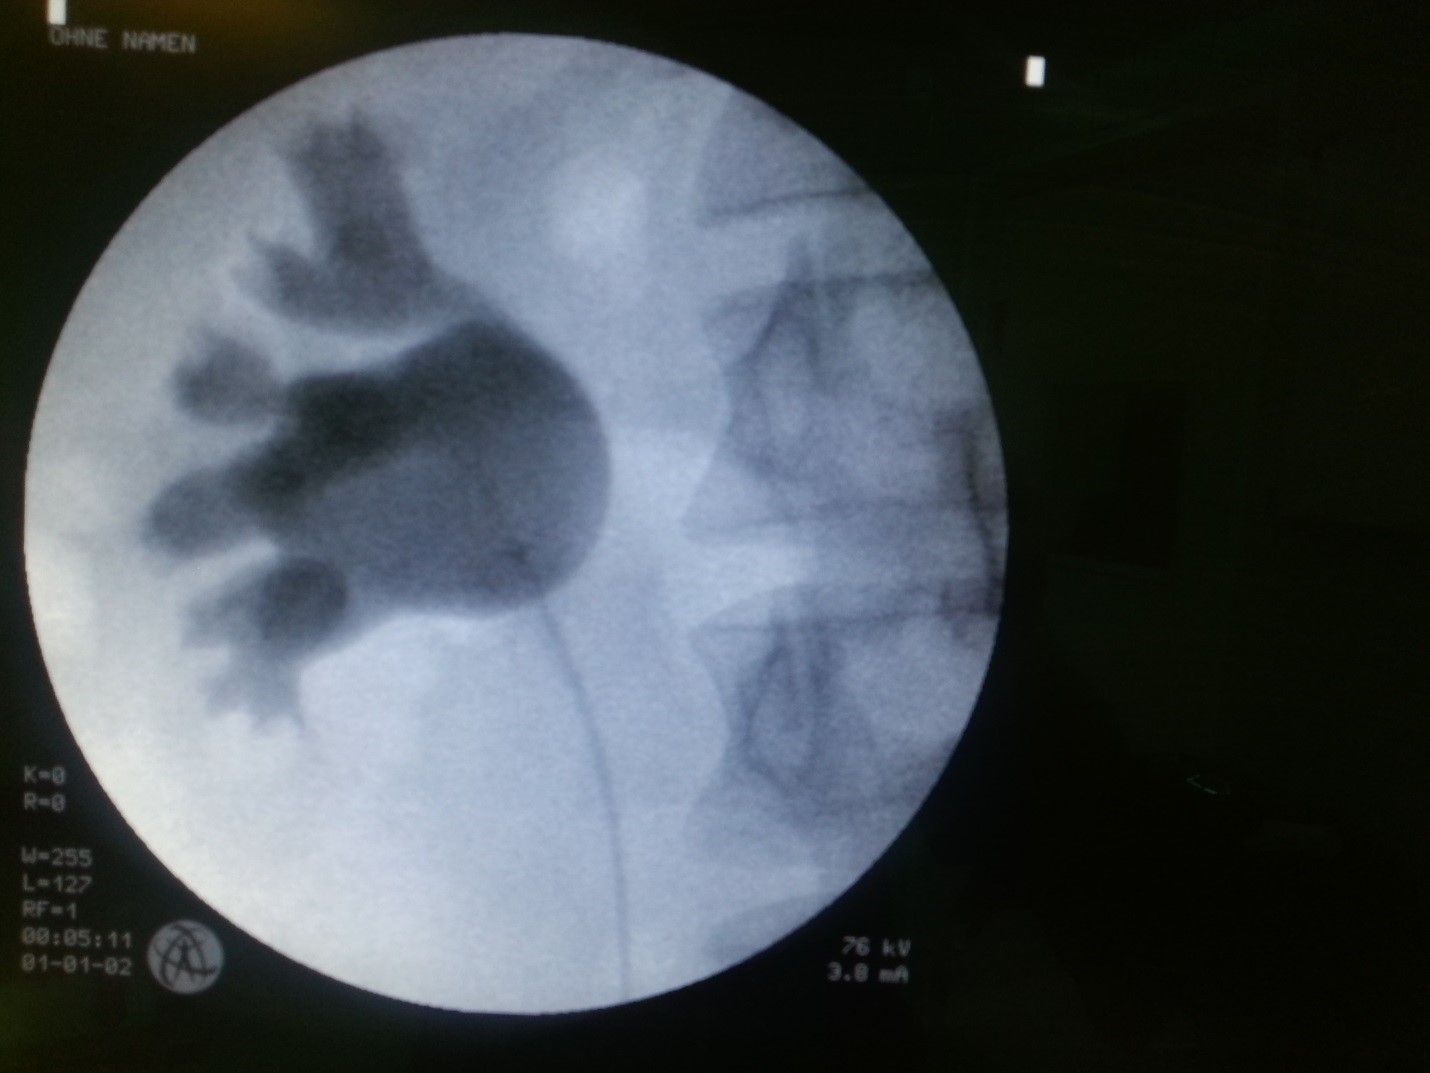

امروزه عمل جراحی باز جهت خروج سنگ کلیه به فراموشی سپرده شده است و عصر شکاف دادنهای بزرگ پهلو و بستری شدن چندین روزه در بیمارستان به سر رسیده است. در حال حاضر استاندارد طلایی عمل جراحی سنگ کلیه PCNL است که با استفاده از شکاف کوچک پوستی 1 سانتی